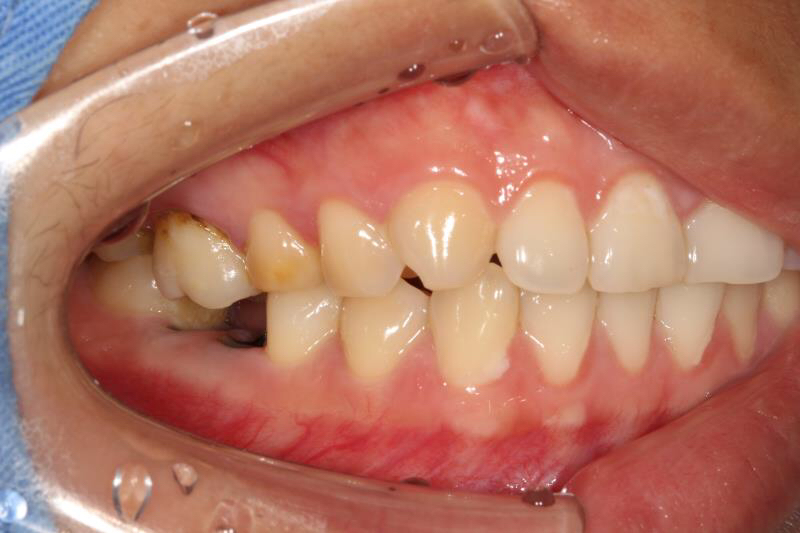

今天给大家介绍一个单颗后牙种植+局部正畸联合治疗病例。

患者年轻女性,后下6残根,因未及时修复,5、7号牙向6号牙倾斜,导致了修复空间不足。按照常规治疗方案,会损伤两侧的健康牙齿,得不偿失,所以我们为她采用了正畸+种植联合治疗方案。